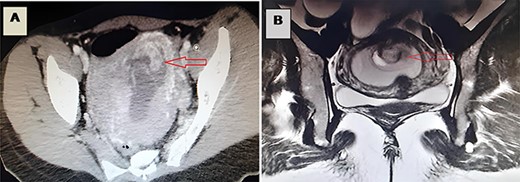

A 29-year-old woman, gravida 1 para 1 (vaginal delivery, 1 child died on the 20th day of life), presented to the emergency department with abdominal pain, nausea and vomiting developed during 5 weeks. She had not passed flatus for 1 week. These symptoms began 1 week after an evacuation of a 6-week pregnancy. Her past medical history was unremarkable. On initial physical examination, the patient was conscious, hypotensive at 90/50 mmHg, tachycardic at 110 p/m, eupneic at 16 c/m, SaO2 95% on room air and apyretic at 37°C.The abdominal examination showed an abdominal distention and tenderness, with diffuse tympany but without any detectable masses. A long-closed posterior cervix was noted with curdled milky secretions on vaginal manual examination. The use of a speculum revealed a normal-looking cervix with a delivered polyp through the cervix with curdled milky leucorrhea. Biological assessment using blood count found a hyperleukocytosis (15 220/μl) with a normal C-reactive protein and an elevated human chorionic gonadotropin (100 000 UI/l). The pelvic ultrasonography revealed an intrauterine ovular sac, a tubular material in the uterine cavity suggesting an incarcerated bowel. A complementary abdominal and pelvic computed tomography (CT) scan was performed (Fig. 1A, Supplementary Video 1), completed by an magnetic resonance imaging (MRI) (Fig. 1B, Supplementary Video 2). They showed a small intestine obstruction due to incarceration of an intestinal segment through a defect in the posterior wall of the uterus, a spontaneously hyperdense uterus and an intra-mural extravasation of the contrast material.

(A) A CT image revealing incarceration of a loop through a defect in the posterior wall of the uterus; (B) an MRI image revealing incarceration of a loop through a defect in the posterior wall of the uterus.